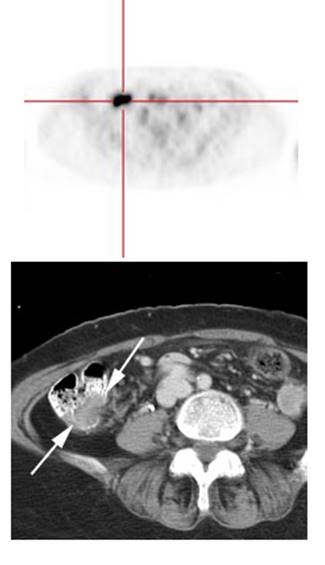

Figure 16 - Focal colonic uptake

associated with colon cancer: This patient had focal tracer uptake in the region of the cecum. CT

demonstrated a soft tissue mass which was found to be a primary colon cancer on

colonoscopy. Focal areas of colonic tracer uptake should be further evaluated.